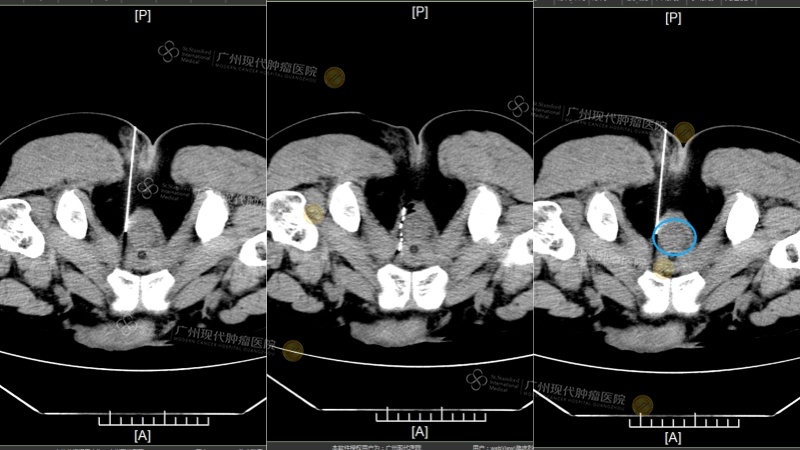

(2024年6月:粒子植入中 VS 粒子植入后 VS 肿瘤位置:此时肿瘤相比已大幅缩小)